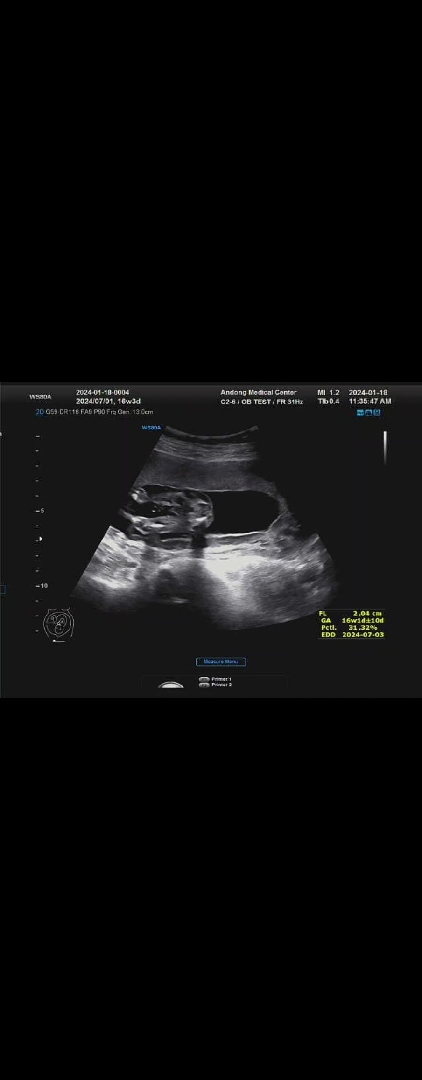

여러분들 보시기에도 아들 맞을까요?ㅎㅎ

14주때는 아이가 다리를 꼬고 있어서 못보고 오늘 처음으로 다리 사이를 보았는데ㅎㅎㅎㅎ 아들 확실하겠죠??ㅎㅎㅎ 오늘 16주 3일입니다!ㅎㅎ